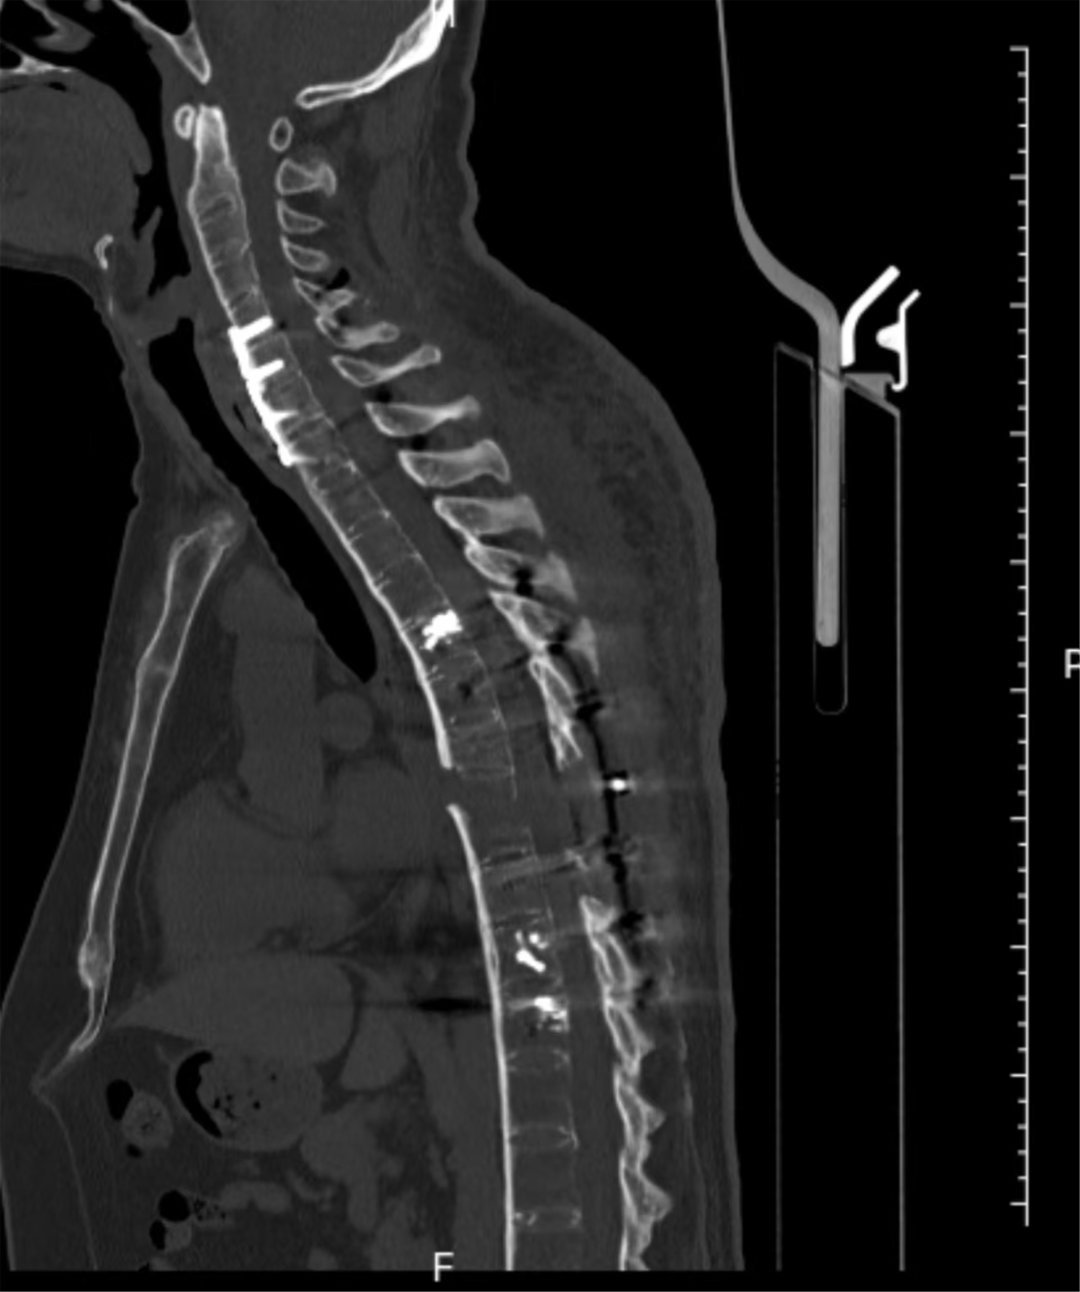

手術當日,多學科團隊嚴陣以待,分階段有序推進。先行仰臥位頸椎閉合復位,再通過頸前5厘米微創切口完成頸椎前路內固定,顯著改善頸椎前方極度不穩定狀況,重建頸椎前柱穩定性。隨后,在神經電生理全程監測下,多學科協同完成Jackson床180°平穩翻轉,成功破解術中核心高危難點。最后,經后正中入路開展頸椎后路固定,并對胸椎骨折完全脫位部位進行減壓、精準復位與牢固內固定,徹底重建頸椎及胸椎脊柱正常序列。

經過13個小時的手術,患者的頸椎及胸椎脊柱序列得以重建

術后,患者經個性化康復治療,脊柱序列恢復正常,無癱瘓及神經功能障礙加重。目前,患者正有序開展康復訓練,即將重返正常生活。